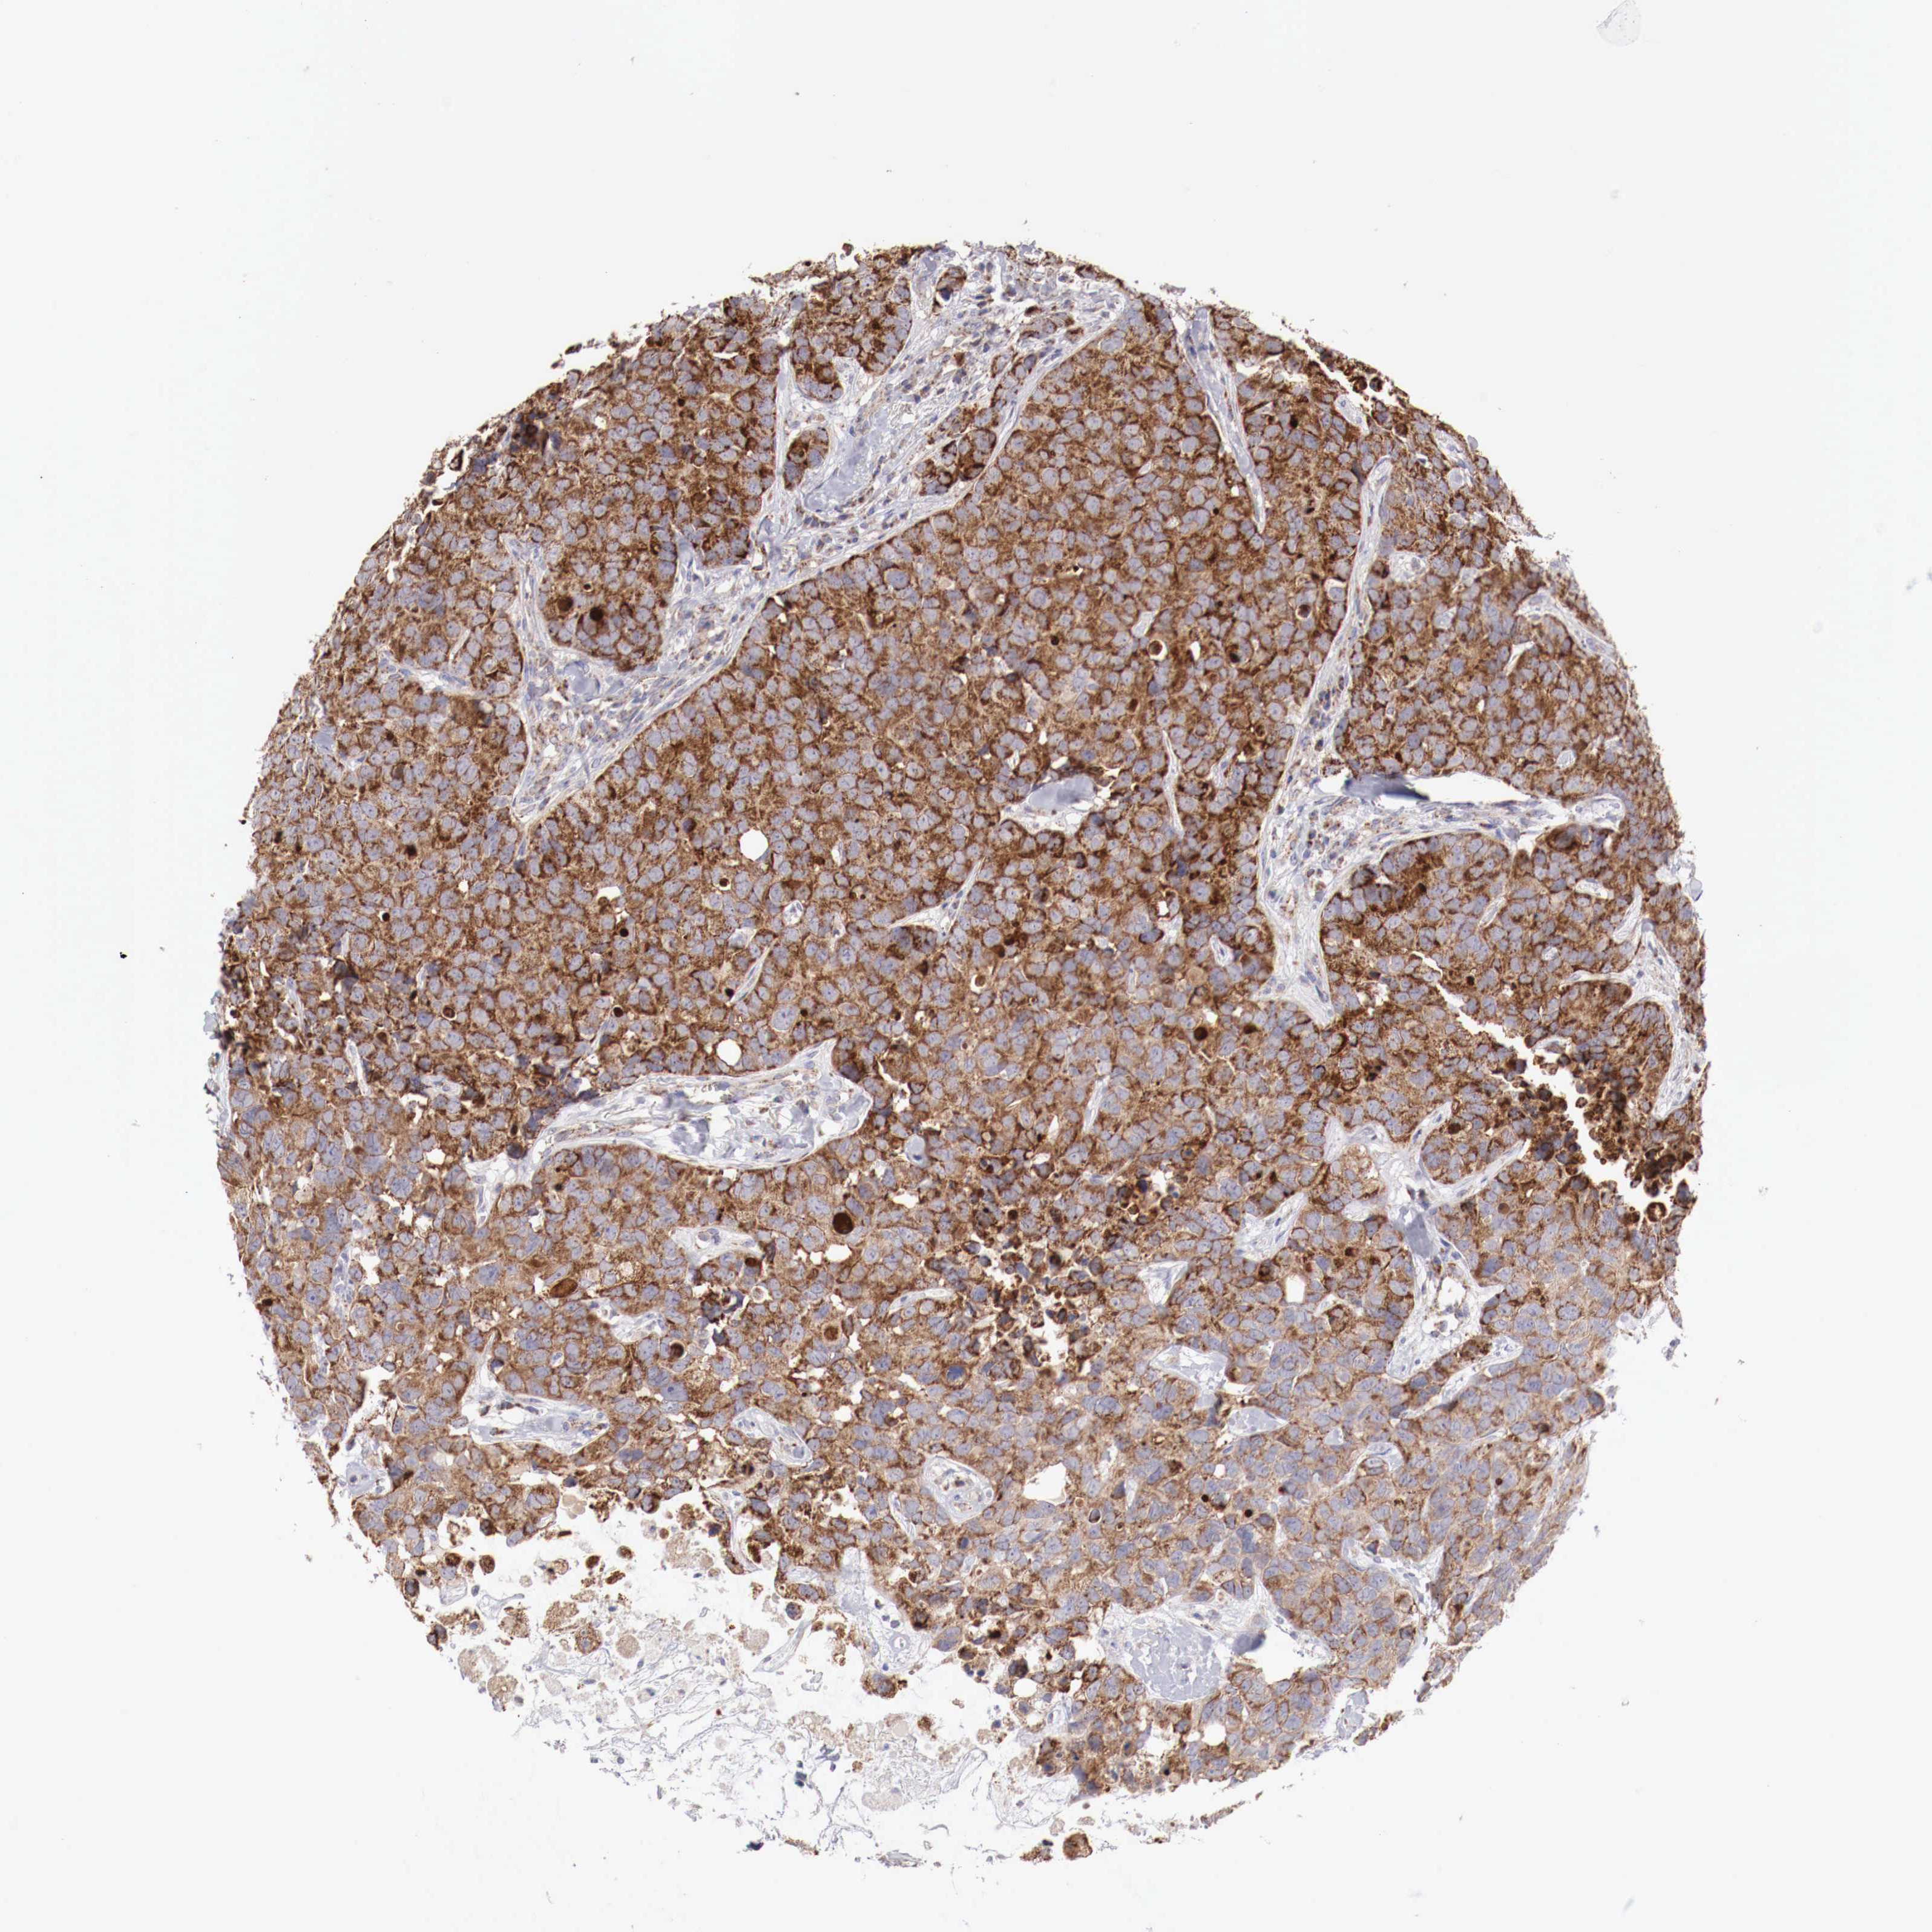

CANCER BREAST CANCER Show tissue menu

BRCA TCGA BRCA VALIDATION PROTEIN EXPRESSION

Breast cancer

Human cancer